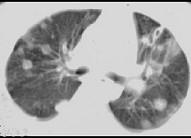

问题 女,32岁,鼻梁双颊部出现红斑伴发热咳嗽2周,肘腕关节游走性疼痛,请结合CT,选择最可能的诊断为 ( )

选项 A.肺部感染 B.结节病 C.肺类风湿病 D.SLE肺部浸润 E.韦格肉芽肿

答案 D